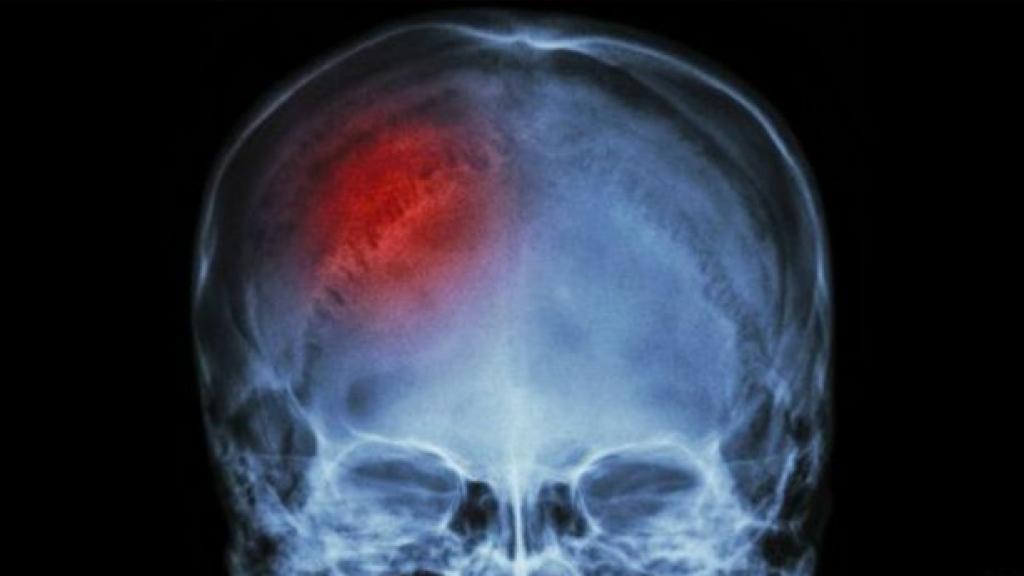

Imagen de un derrame cerebral.

El ictus o accidente cerebrovascular es una de las principales causas de mortalidad en España, siendo la segunda causa de muerte en general, pero la primera causa en mujeres. A todos estos datos hay que sumar el hecho de que se calcula que al menos el 90% de los casos de ictus podrían evitarse, según la Sociedad Española de Neurología.